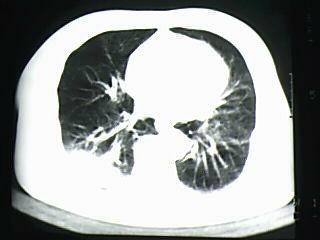

标题: CT19768:男 61岁 胸痛 咯血 一周。无发烧、无结核病史。 [打印本页]

标题: CT19768:男 61岁 胸痛 咯血 一周。无发烧、无结核病史。

右下肺中心型肺癌

右下肺支气管扩张

纵隔窗图像不佳,怀疑右下叶支气管有狭窄,来几张清楚的,暂考虑----感染性病变----抗炎后复查

考虑 右下肺感染性病变,建议抗炎后复查。

考虑右肺下叶感染性病变;建议抗炎治疗后复查。

考虑右肺下叶感染性病变,建议抗炎治疗后复查。

右下肺感染性病变,建议抗炎后复查。支持